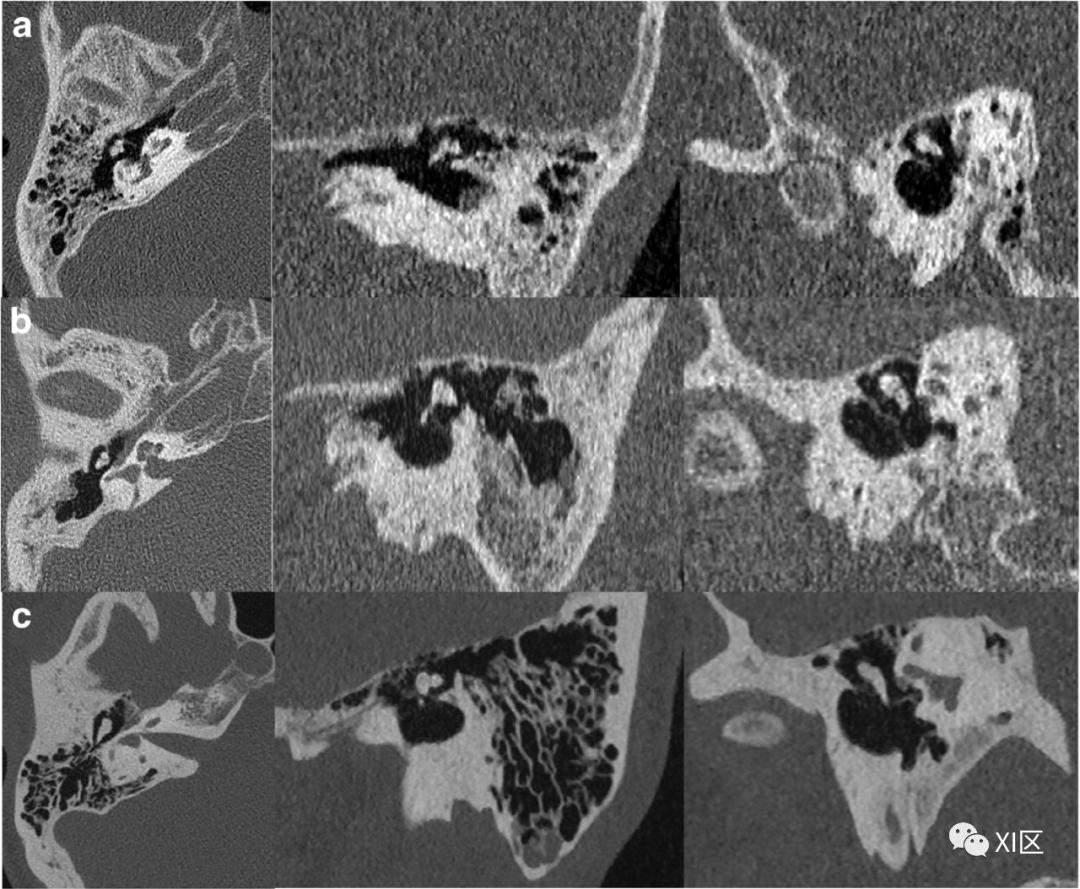

ZUHR和第三代双源UHR技术比较。第一代双源(A),第二代双源(B)和第三代双源(C)内耳图像比较。注意使用0.4x0.5 mm的小焦点第三代双源UHR模式图像质量显著改善。层厚均为0.4 mm。

Initial results of a new generation dual source CT system using only an in-plane comb filter for ultra-high resolution temporal bone imaging[J]. European Radiology, 2015, 25(1):178-185.